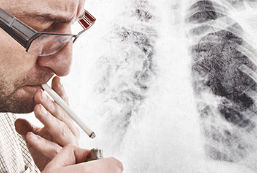

폐암은 국내 암 사망률 1위인 무서운 질병입니다. 특히 흡연자분들이라면 더욱 주의 깊게 살펴보셔야 하는데요. 담배연기 속 유해물질 중 발암물질 함량이 높기 때문에 지속적으로 노출될 경우 폐암 발병 확률이 높아집니다. 하지만 초기에 발견하면 완치율이 높은 편이기 때문에 미리미리 예방해야 합니다. 그래서 오늘은 폐암 초기증상과 예방법에 대해 알아보겠습니다.

금연: 가장 중요한 폐암 예방 방법은 흡연을 피하는 것입니다. 흡연은 폐암의 가장 큰 원인 중 하나이며, 흡연자들은 폐암 발병 위험이 훨씬 더 높습니다. 흡연을 하지 않거나 흡연을 중단하는 것이 가장 효과적인 방법입니다. 흡연자는 금연을 위해 의료 전문가의 도움을 받을 수도 있습니다.